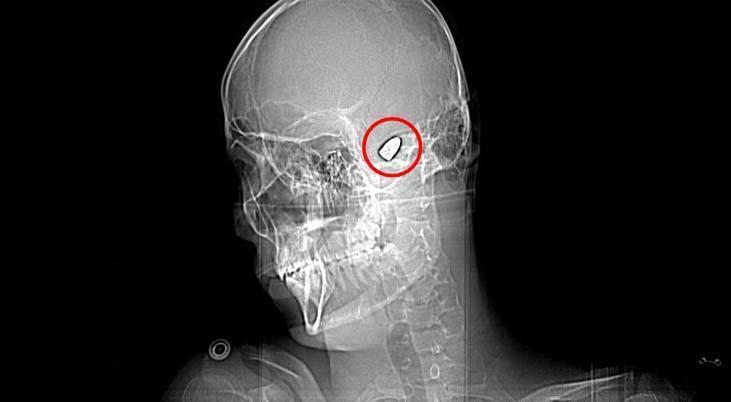

Olay, 5 Kasım 2023’te Bahçelievler Mahallesi 1624’üncü Sokak’ta meydana geldi. Arkadaşları ve ağabeyiyle maça gitmek için konutundan çıkan Yusuf Emre Özbek, birlikte fotoğraf çektirdikten çabucak sonra yere yığıldı. Etraftakilerin hastaneye götürdüğü Yusuf’un çekilen röntgeninde, başında mermi çekirdeği olduğu tespit edildi.

4 gün ağır bakım, 4 gün de serviste tedavi gören Yusuf’un başındaki mermi için hekimler, riskli bölgede olduğu gerekçesiyle müdahale etmedi. Nizamlı olarak denetim edilen Yusuf’ta konuşma zahmeti ve sağ el ve parmaklarında zayıflık belirtileri ortaya çıkınca, fizik tedavi süreci başladı.